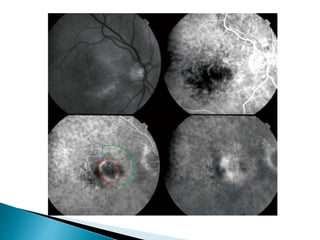

 Classic CNV

 Occult CNV

 Retinal angiomatosis proliferans

 These types are recognized by doing a FFA

 An area of well demarcated hyper fluorescence in the

early phase

 These are discrete and bright

 Pooling of the dye due to leakage in the sub sensory

retinal layer

 Here the new vessels extend between the basement

membrane and RPE

 Signs of pigment epithelial detachment

 Late leakage from undetermined source

 The hyper fluorescence seen here is not as discrete and

bright as in classic CNV, but it is stippled

 Late leakage from undetermined source appear as

pooling of the dye in which the point source of leakage

which can be seen as discrete hyper fluorescent spot is

not seen here